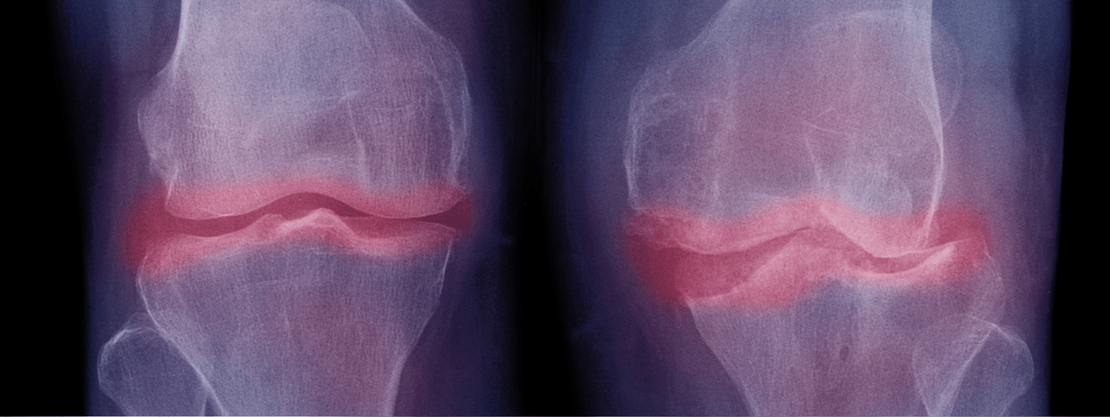

Diagnóstico avanzado de imagen Musculoesquelética

Mediante técnicas radiológicas de última generación, puedo ofrecer diagnósticos precisos en una amplia gama de condiciones que afectan los huesos, las articulaciones, los ligamentos y los músculos.

Esto incluye, pero no se limita a, diagnósticos de

lesiones deportivas, trastornos degenerativos y patologías inflamatorias. Mis servicios de diagnóstico están respaldados en su gran mayoría de veces, por la tecnología de ecografía de alta resolución que permite visualizaciones claras y detalladas, facilitando diagnósticos más precisos y rápidos.